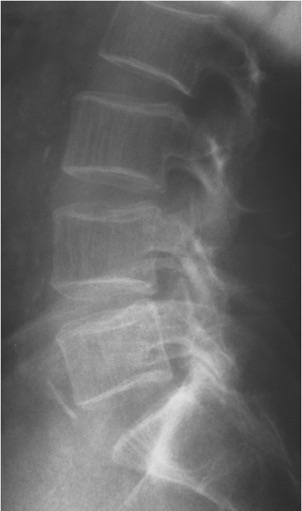

LUMBAR SPINE:

Frontal and lateral views are submitted.  Viewed coronally, there is a mild left convexity with the apex at L3.  The left femoral head and iliac crest are lower than the right by 12mm.  Viewed sagittally, the upper lumbar spine is slightly hypolordotic.

Bone density is moderately diminished, with increased lucency of all osseous structures and vertical striations in the vertebral bodies.  Mild osteophytic proliferation is seen on the vertebral bodies from L2 through L5.  Calcific plaquing is visible along the course of the abdominal aorta.

IMPRESSIONS:

1.	Atherosclerosis.

2.	Moderate osteoporosis.  Follow up is recommended.

3.	Mild spondylosis, L2 through L5.

4.	Apparent 12mm short left leg.  Clinical correlation is recommended.

5.	Postural alterations as described above.

RECOMMENDATION:

1.	The osteoporosis is most likely related to the patient’s age, however the possibility of an aggressive osseous destructive process cannot be ruled out on the basis of these films alone.  Clinical correlation and consideration of referral to GP for further investigation is recommended.